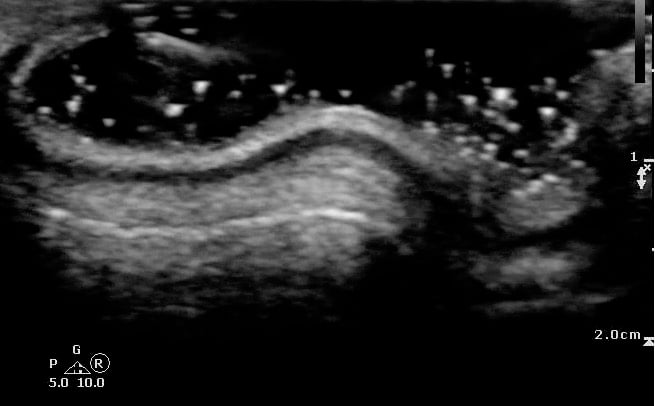

- Figure 1 and 2. Normal Ear

Video 1. Normal Ear - Anterior and posterior skin layers have thin hyperechoic appearance.

- Middle layer containing cartilage appears as a thin hypoechoic band.

- At the antihelix border the cartilage is thicker; the mean thickness is 0.8 ± 0.1 mm (at the middle third of the antihelix in transverse axis).

- At the lobule the mean thickness is 6.9 ± 1 mm.